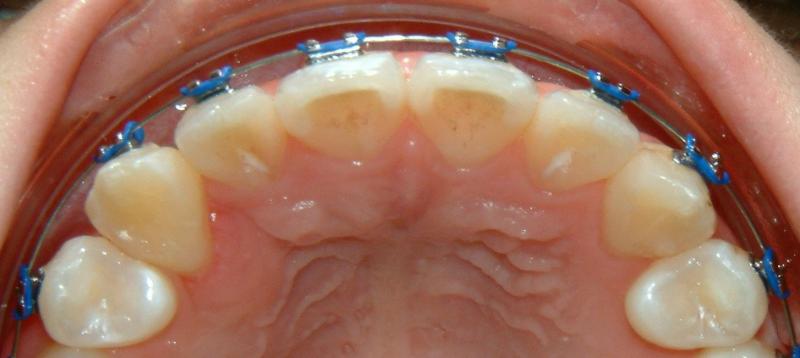

Without surgical exposure and forced eruption, there was practically very little progress with natural eruption of the upper right canine for nearly 3 years (not shown). With the surgical exposure (laser -> no bleeding) and forced eruption, the progress can be seen almost immediately - within a month (Fig. 9). After 2 months, the crown is more visible: part of the crown can be seen clearly (Fig. 10). After 8 months, the crown is moved into the position (Fig. 11). With additional 3 months, the crown is relatively well leveled and aligned (Fig. 12). It takes longer to treat the palatally impacted canine.

Fig. 9 Forced eruption, 1 month after laser surgery (progress)

© Copyright 2007-2014, Vu Orthodontics. All rights reserved.